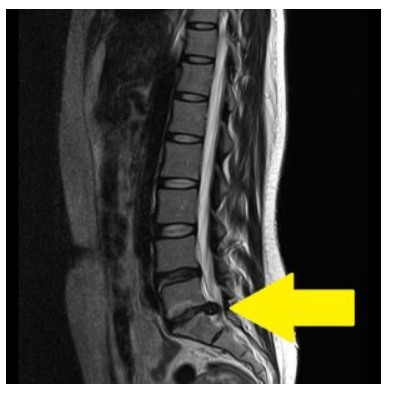

1. 腰部脊柱管狭窄症

メカニズム 脊柱管(神経の通り道)が加齢により狭くなり、神経が圧迫される状態。MRI検査で診断されることが多い。